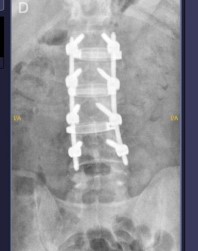

La Cirugía XLIF es una técnica mínimamente invasiva de fusión vertebral que se realiza a través de un acceso lateral, evitando incisiones en la parte anterior o posterior del tronco. Se utilizan instrumentos especializados y monitorización neurológica en tiempo real para proteger estructuras nerviosas y musculares, logrando una fusión vertebral eficaz con menor trauma quirúrgico

Fusión vertebral confiable, con tasas de éxito similares a técnicas abiertas y tasas de complicaciones inferiores

Restauración de la altura del disco intervertebral y corrección de curvatura vertebral (lordosis) en casos adecuados.